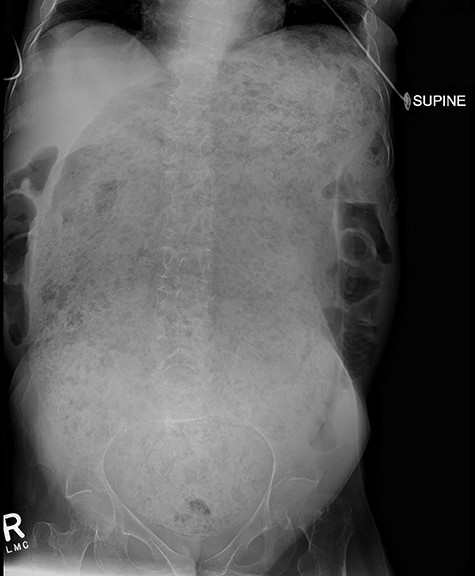

A 64-year-old female who resides in a nursing facility due to significant mental and physical disability presented to the emergency department with a 4-month history of chronic intermittent constipation. She had been treated multiple times for severe constipation and fecal impaction. On presentation, abdominal X-rays exhibited massive stool burden filling the rectum, which was distended cephalad to the diaphragm and anteriorly to the peritoneum occupying much of the abdominal cavity (Fig. 1). The patient was admitted to the hospital and aggressive bowel regimen was initiated with limited improvement. Given a history of multiple failed attempts with pharmacological therapy, surgical intervention was considered. A computed tomography scan of the abdomen showed a massive amount of stool in the rectosigmoid colon with no evidence of an obstructing lesion. The patient had undergone colonoscopy within 2 years of presentation with no evidence of polyps or malignant process. She was chronically malnourished, bedbound, non-communicative putting her at significant risk of morbidity with major intervention. Risks and benefits were discussed with the patient’s family, and it was opted for the least invasive surgical approach. We proceeded with creation of a loop colostomy of the descending colon through a mini left to midline 2.5 cm incision. The patient tolerated the procedure well. Post-operatively, she was treated with antegrade enemas through the distal limb of the colostomy as well as enemas and suppositories per rectum. Subsequent X-rays showed significant decrease in stool burden over the 14-Day period (Fig. 2). She was ultimately discharged to her nursing facility with normal bowel function.

Demonstrates massive megarectum secondary to large stool burden in context of chronic constipation.